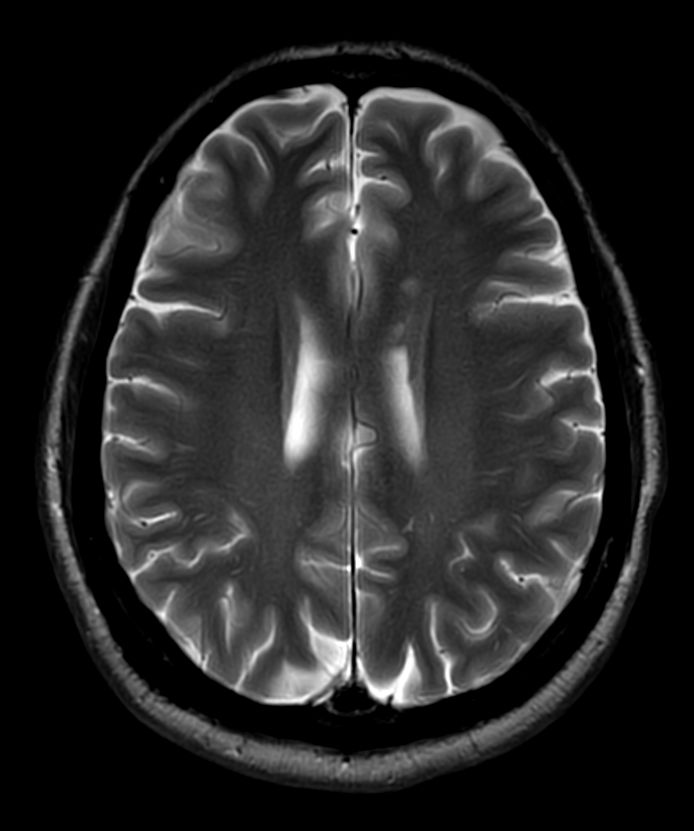

T2w TSE MultiVane XD